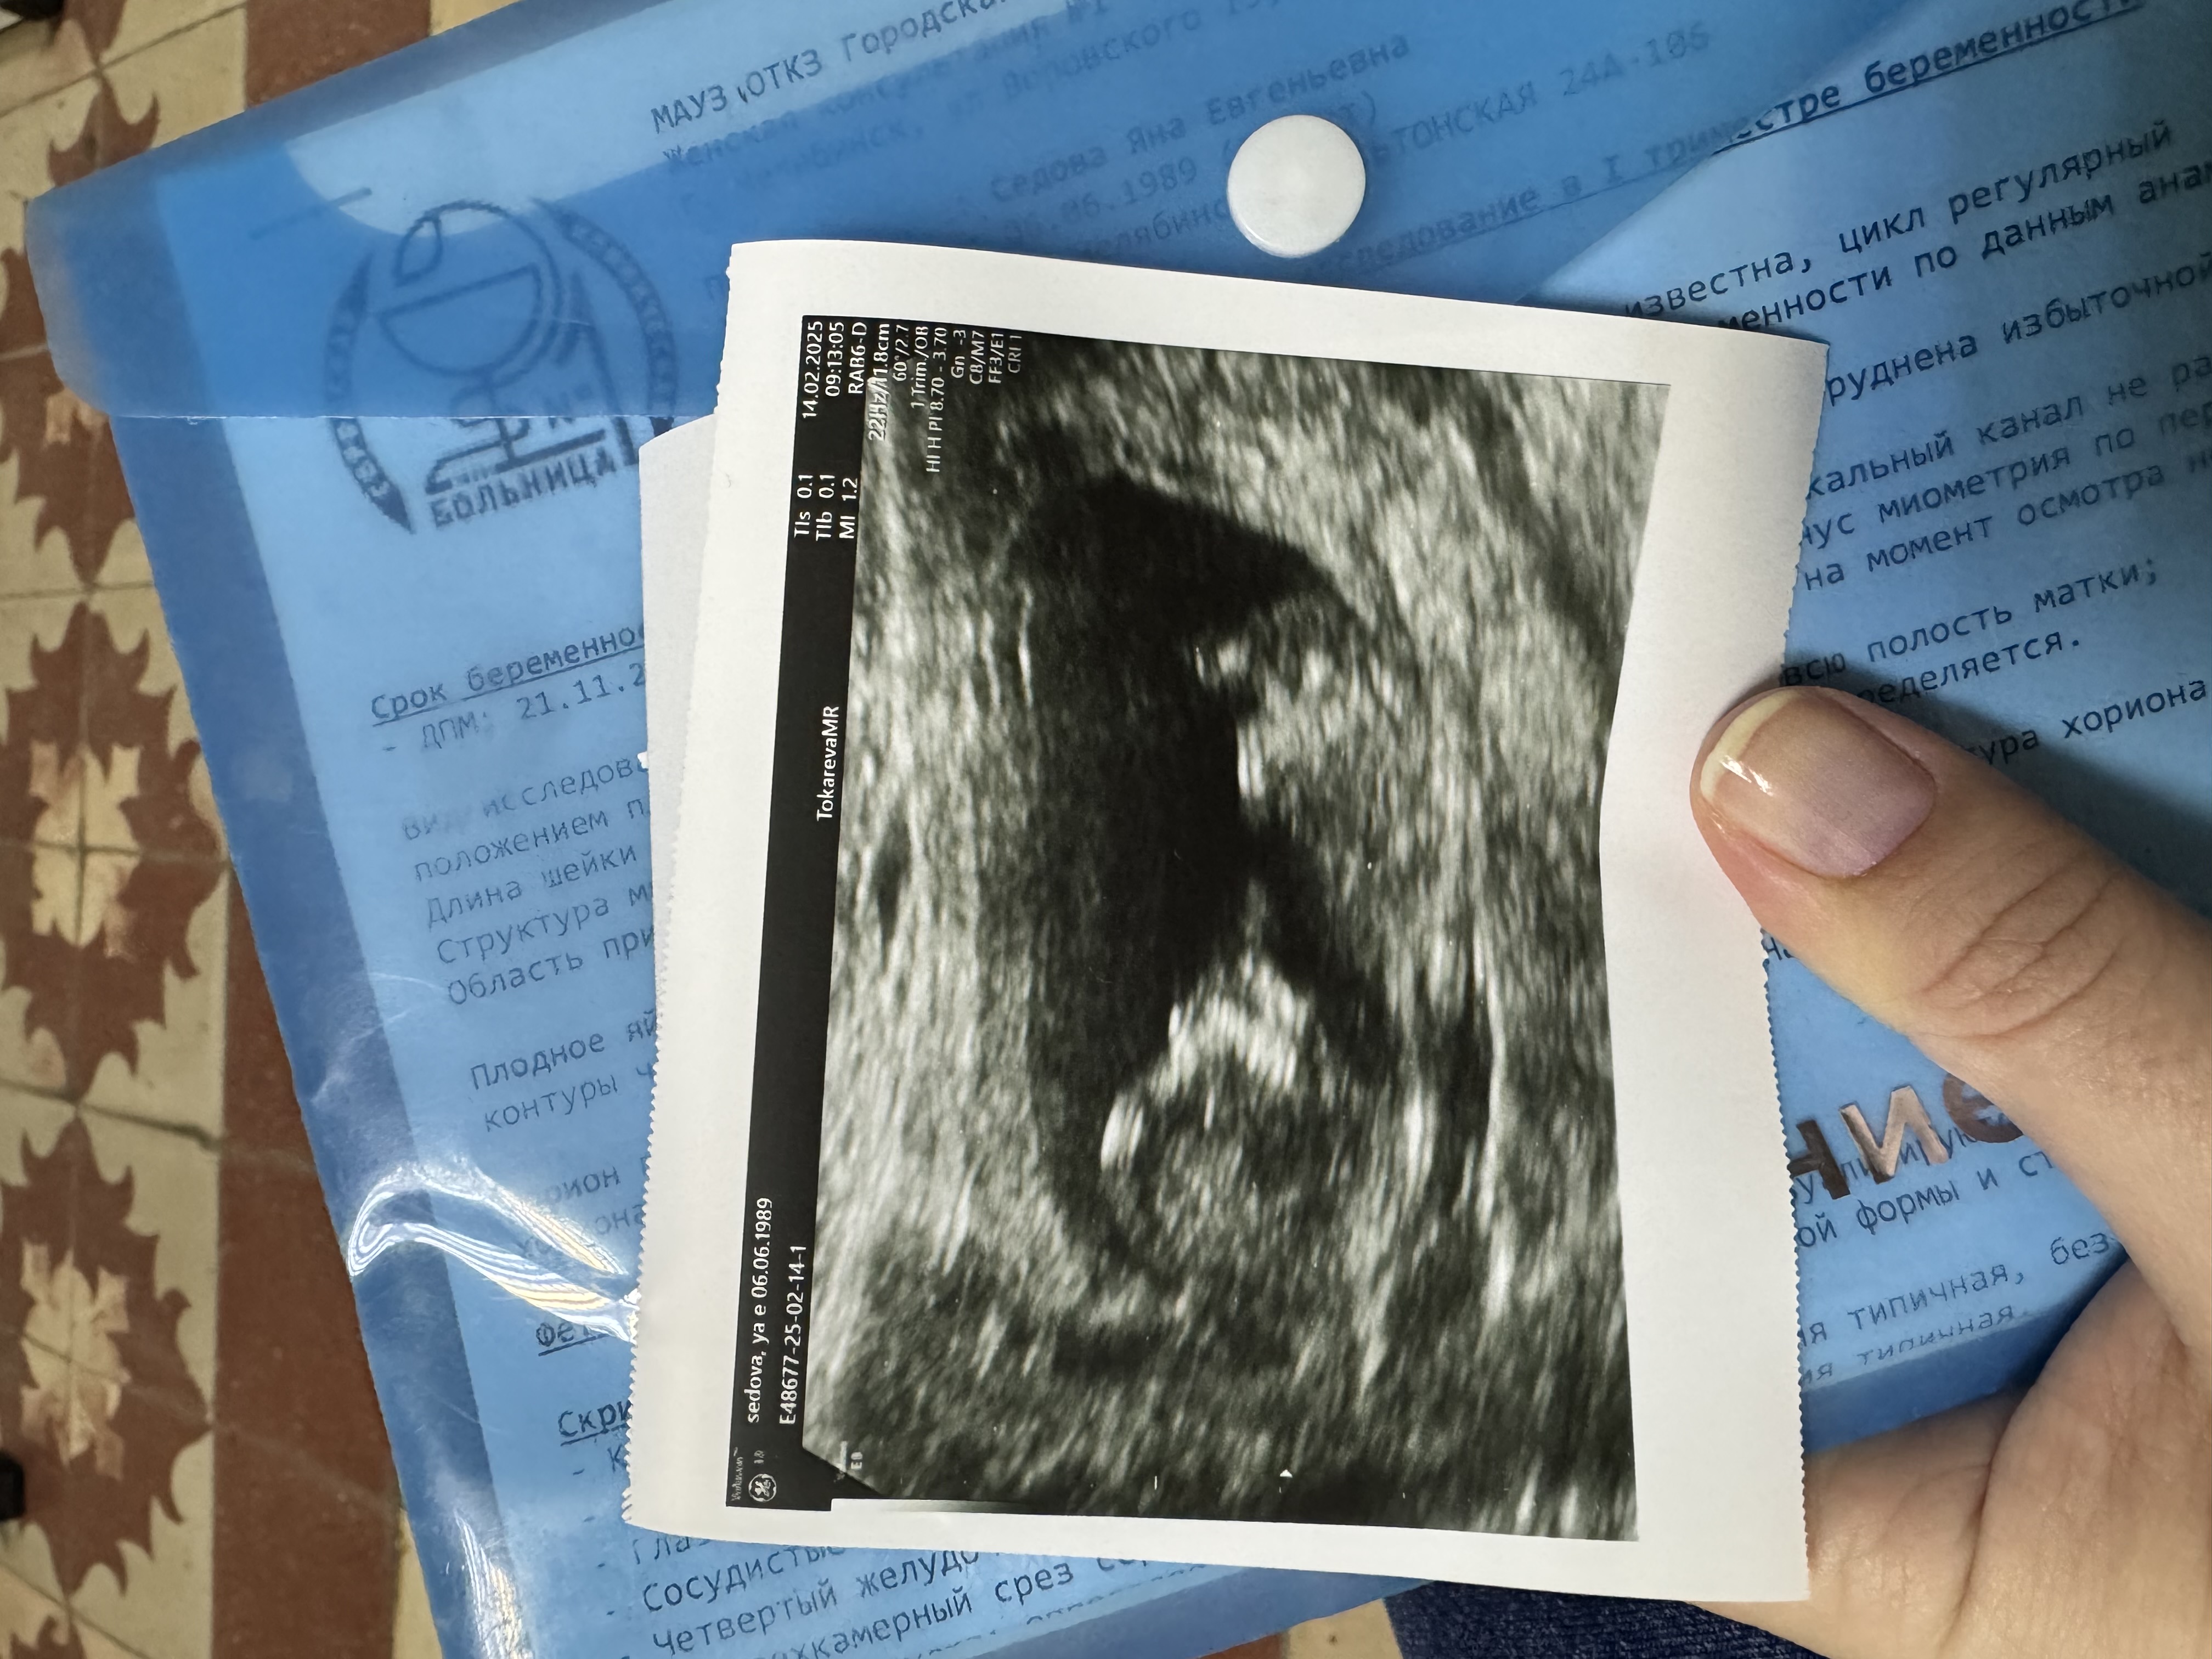

Скрининг риски

Девочки всем привет! Подскажите, кто знает. Сегодня была на 1м скрининге - врач узи сказал, что все в пределах нормы. Меня заинтересовали такие показатели как преэклампсия до 37 недель риск 1:66 и преэклампсия до 42 недель 1:11 - что это значит, не могу никак понять(((

Пол малыша конечно не увидели, малыш так отмахивался от датчика узи, см